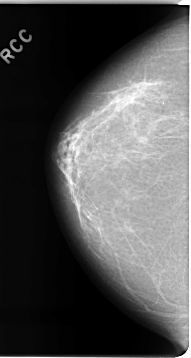

C_0075_1.RIGHT_CC

RIGHT_CC LINES 4648 PIXELS_PER_LINE 2472 BITS_PER_PIXEL 12 RESOLUTION 50 NON_OVERLAY

FILE: C_0075_1.LEFT_CC.OVERLAY

TOTAL_ABNORMALITIES 1

ABNORMALITY 1

LESION_TYPE MASS SHAPE IRREGULAR MARGINS SPICULATED

ASSESSMENT 5

SUBTLETY 5

PATHOLOGY MALIGNANT

TOTAL_OUTLINES 1

BOUNDARY